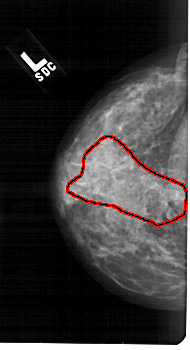

A_1851_1.LEFT_MLO

LEFT_MLO LINES 5476 PIXELS_PER_LINE 2941 BITS_PER_PIXEL 12 RESOLUTION 43.5 OVERLAY

FILE: A_1851_1.LEFT_MLO.OVERLAY

TOTAL_ABNORMALITIES 1

ABNORMALITY 1

LESION_TYPE CALCIFICATION TYPE PLEOMORPHIC DISTRIBUTION SEGMENTAL

ASSESSMENT 4

SUBTLETY 3

PATHOLOGY MALIGNANT

TOTAL_OUTLINES 1

BOUNDARY